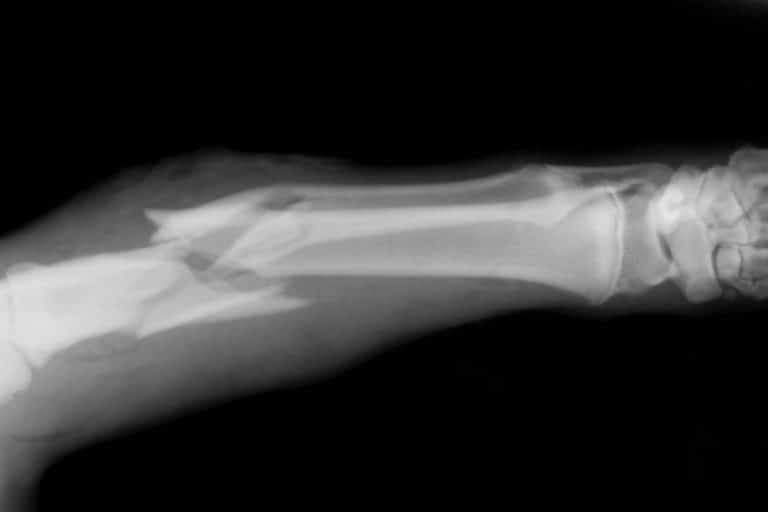

Broken bone cases are considered serious injuries because of the potential long-term effects they can have on an individualโ€™s future ability to work and quality of life. Fractures can be the result of a workplace accident, especially on construction sites, however, that is not to... (Keep Reading)

How To File A Broken Bone Injury Claim In New York City